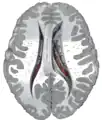

Central part and anterior and posterior cornua of lateral ventricles exposed from above.

Coronal section through anterior cornua of lateral ventricles.